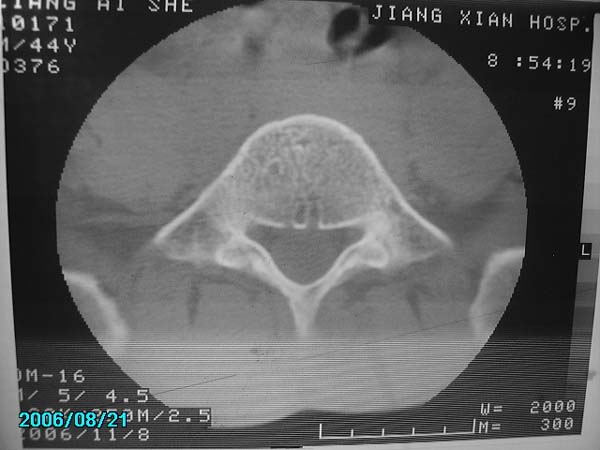

男,40岁,腰疼半年

腰4-5椎间盘后缘变平直,可考虑椎间盘轻度突出。余未见异常。

腰4-5椎间盘轻度突出。余未见异常。

腰4-5、腰5-骶1椎间盘后缘变平直,可考虑椎间盘轻度突出。余未见异常

除有第3-5腰椎椎体后缘中央血管沟显示外,诸椎间盘比较正常。我也象13081830109战友那样看见了指纹,呵呵。